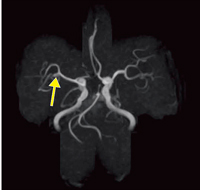

■症例1:未破裂右中大脳動脈瘤

70歳,女性。ときどき感じる手のしびれを訴えて来院。MRAにて径5mmの未破裂右中大脳動脈瘤を認める(↑)。 MRA,3D TOF(MIP),FOV:160mm, TR/TE:37/6.5,FA:30°,スライス厚:1.2mm